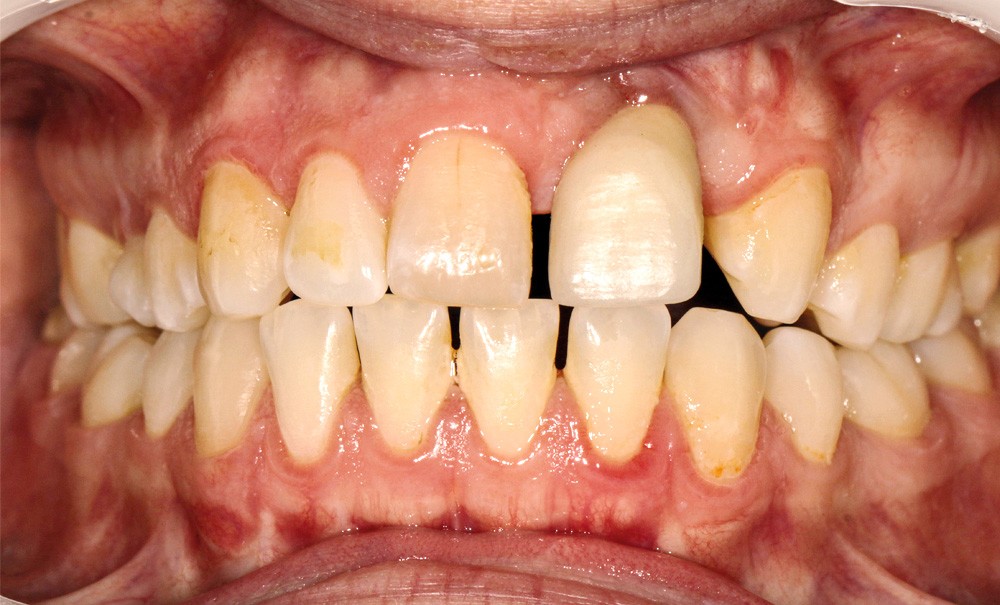

- au niveau dentaire : une arcade maxillaire asymétrique avec déviation du milieu maxillaire à gauche. On note l’absence de 21, 22, 25, 35 et 45, une classe II droite et gauche avec infraclusion antérieure et la présence d’un implant en place de 21 avec un diastème de 3 mm entre 21 et 23 (fig. 3) ;

- au niveau fonctionnel :une déglutition atypique avec interposition linguale entre les arcades dentaires.